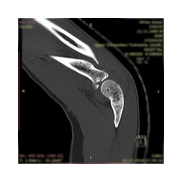

Görüntüleri büyütmek için resmin üstüne tıklayınız.